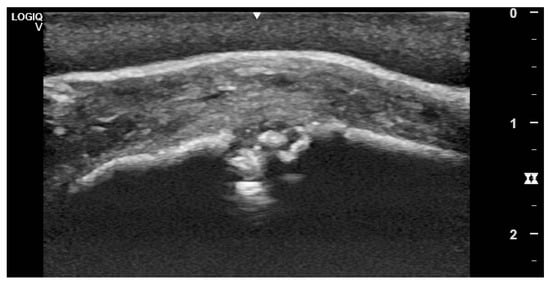

3.2. Imaging Findings